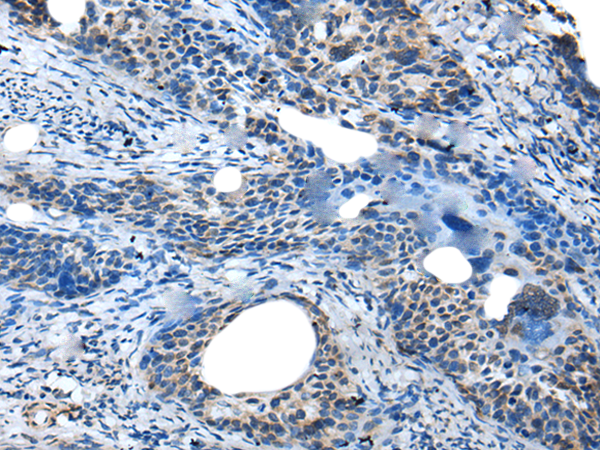

IHC positive control: |

Human cervical cancer |

IHC Recommend dilution: |

25-100 |